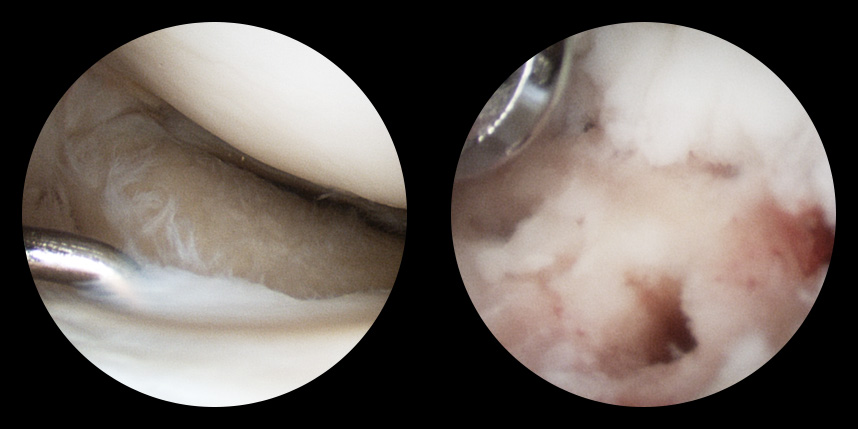

손상된 연골 부위에 작은 구멍을 뚫어 골수에서 나오는 줄기세포를 이용하여 연골 재생을 유도하는 방법으로 근본적으로 섬유연골(정상연골보다는 약한 연골)로 재생된다고 알려져 있습니다.

특수하게 농축하여 제작된 6% 콜라겐(리젠실603) 또는 9% 콜라겐(이엔카티)을 천공술을 시행한 부위에 덮어 주어 미세천공술 단독보다 좋은 치료 결과를 기대할 수 있습니다.

본원에서는 미세천공술, 콜라겐주입술, 카티스템 치료를 주로 하고 있습니다.

연골 손상이 크거나 작고 어느 위치에 있어도 연골재생술이 가능합니다.

전통적으로 증명이 된 미세천공술을 항상 같이 시행